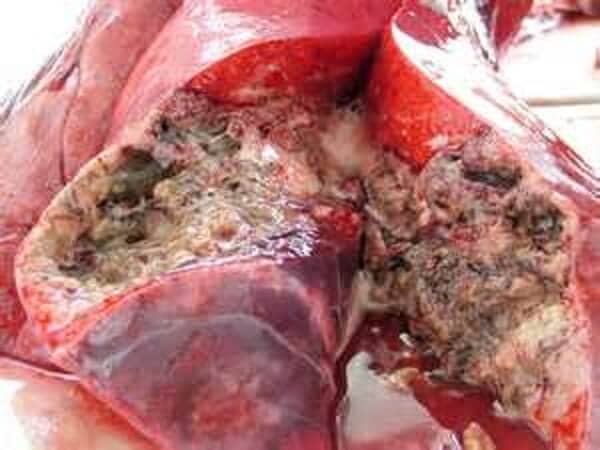

Wissen Sie, wie viele Menschen im Jahr durch eine Pilzinfektion ums Leben kamen? Insgesamt starben im Raum München im vergangenen Jahr 55.000 Menschen. 31.000 davon hatten einen Fußpilz. Das entspricht mehr als der Hälfte aller Gestorbenen. Nagelpilze beeinträchtigen nicht nur unsere Zehennägel, sondern dringen in den Blutkreislauf ein und verbreiten sich so über den Fuß in den gesamten Körper. Der Pilz zerstört unseren Körper von innen heraus und sorgt bei allen Organen für Stress. Die kleinen Sporen heften sich an die inneren Organe an und vermehren sich, wodurch Schäden entstehen. So sind auch innere Organe von der Pilzinfektion betroffen. Das bedeutet, dass der Körper von innen heraus "verfault". Im Laufe der Zeit versagt das Herz, ein Blutgefäß im Gehirn kann explodieren oder es kann zu Leberkrebs kommen. Auch ein Nierenversagen ist möglich. Jeder, der an Nagelpilzen leidet, hat dieses Risiko. Das Immunsystem wird durch häufige Erkältungen geschwächt und der Stress tut sein Übriges, was zum plötzlichen Tod führen kann.

Aus diesem Grund sehe ich Nagelpilze als eine extrem gefährliche Krankheit an, die bundesweit für eine Vielzahl der Tode verantwortlich ist. Wir hören oft von Krebs und Tumoren, doch letztendlich betrifft das nur 3 bis 4 Prozent aller Menschen, wohingegen Nagelpilze bei 50% aller Menschen im Alter von 40 bis 45 Jahren vorhanden sind.

Das Produkt kann Nagelpilze vollständig zerstören, indem die äußeren Symptome entfernt und der gesamte Körper gereinigt werden. Schon ab dem ersten Tag reduziert das Mittel das Risiko des plötzlichen Todes auf quasi 0%. Durch die Verwendung dieses Mittels können Betroffene aufatmen. Der Blutkreislauf sowie die inneren Organe werden von den Pilzzellen befreit, sodass die Infektion, die sonst langsam bis zum Tode geführt hätte, abklingt.

Das Geheimnis der Effektivität liegt im Design des menschlichen Körpers begründet. Nagelpilz ist deswegen so hartnäckig, weil er im Gewebe sitzt. Wird ein Medikament nicht mehr eingenommen, tritt der Pilz wieder auf. Ein weiteres Problem ist, dass das Immunsystem den Pilz nicht selbst bekämpfen kann. Im besten Fall kann es die Entwicklung der Infektion nur verlangsamen. Ein schwaches Immunsystem kann das schnelle Wachstum der Pilze nicht verhindern, was früher oder später zum Tod führt.

Exodermin neutralisiert die Infektion, indem die Pilzpartikel im Blut und in den inneren Organen zerbrochen werden. Dadurch kann sich die Infektion im Körper nicht weiter ausbreiten, was zu einer vollständigen Genesung führt. Sämtliche Spuren der Infektion werden beseitigt und der Patient kann wieder ein gesundes Leben führen. Der Körper entwickelt zudem eine Immunität gegen die Pilze, wodurch keine erneute Infektion möglich ist.